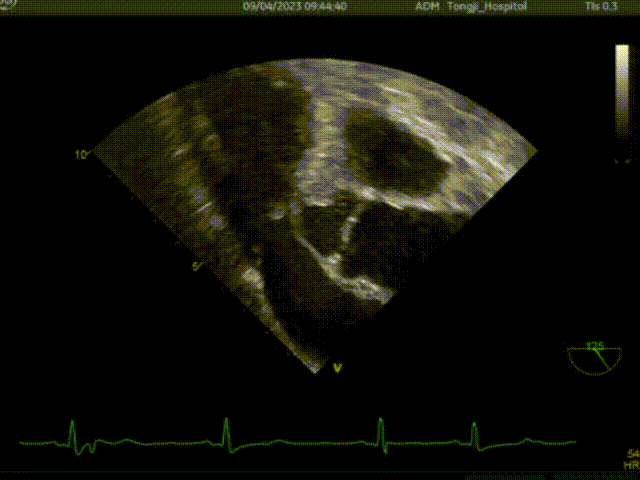

术前超声TEE检查结论:

1. 左室非对称性肥厚,左室流出道梗阻,二尖瓣重度关团不全;

2. 二尖期后叶脱垂;

3. 卵圆孔未闭(极细缝隙)。

患者术前大量反流,前叶SAM征,室间隔增厚最厚处13mm